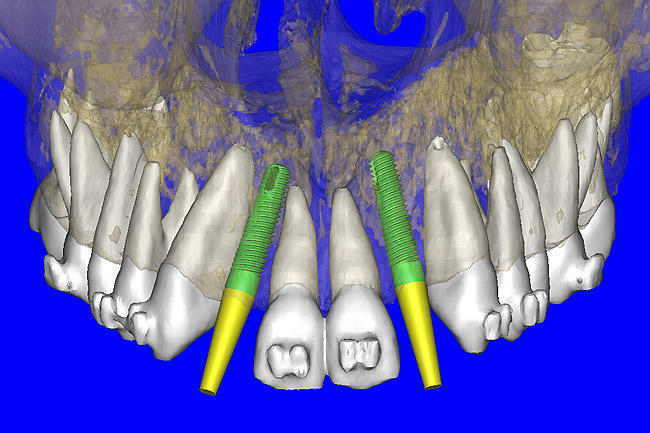

After the basic plan had been established, it was re-evaluated using interactive 3D images. The reconstructed 3D view of the maxilla clearly illustrated the extent of the bilateral facial concavities, and the root eminences of the adjacent and posterior teeth (Figure 7A). The placement of the virtual implants then was evaluated to ensure that the facial cortical plate was not perforated (Figure 7B). The implants were labeled individually as “7” and “10,” with the simulated yellow abutment projection indicating the facial-lingual inclination through the bone to the level above the incisal edge of adjacent teeth. The ability to gain a better understanding of these individual root forms can not be underestimated. The dental literature has suggested certain parameters for placing implants near teeth and implants next to other implants. However, there is little scientific 3D documentation to support these suggested rules.5-10 The use of an interactive treatment-planning software application permits closer scrutiny of previously difficult-to-visualize areas, and can now be used to redefine perceptions of spatial positioning of implants, especially when in close proximity to natural tooth roots, vital anatomy, and adjacent implants.27-29

Using different masking (segmentation) and threshold Hounsfield unit values, several new 3D bone volumes can be created which offer invaluable information. To help determine the final position of each implant a new bone model was created with a Hounsfield unit value of 1480, which eliminated all but the densest objects included in the scan data. (Results may vary depending on the CBCT machine used.) The inner and outer layers of bone were removed, leaving the underlying enamel and root structure of the teeth (Figure 8A). After the bone had been stripped away, the root inclinations were examined closely. The most striking findings confirmed the rotated position of the right central, while revealing the slight mesial dilaceration of the root apex, which converged on the space needed for the path of the potential implant (Figure 8B). The schematic shapes of the proposed implants were visualized for the right and left lateral spaces in different rotations of the 3D maxillary arch. It was at this point that a determination was made as to the appropriate implant shape and type that would fit the available space while avoiding encroachment on adjacent tooth roots. A tapered design implant (Tapered Screw-Vent®, Zimmer Dental, www.zimmerdental.com) was chosen from the large virtual library. With the SIMPlant software, the virtual library contains data from dozens of implant manufacturers and realistic.computer-aided design representations as seen in Figure 9A through the translucent bone. The position of the left implant can be visualized with adequate mesial-distal distance between adjacent tooth roots (Figure 9B) and a more delicate placement (Figure 9C).

Figure 7a  The 3D reconstruction showed (A) the facial concavities and root eminences, and allowed (B) for evaluation of virtual implant placement to ensure the facial cortical plate was not perforated.

Figure 7a

Figure 7b  The 3D reconstruction showed (A) the facial concavities and root eminences, and allowed (B) for evaluation of virtual implant placement to ensure the facial cortical plate was not perforated.

Figure 7b